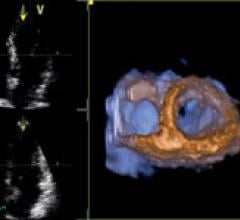

Hardware and software advances are enabling echocardiography to greatly expand its capability with increased quantification accuracy, ease-of-use, increased workflow efficiencies and wider use outside of echo labs. Today, cardiovascular ultrasound systems are being integrated into point-of-care for triage, and in operating rooms and cath labs for procedural guidance to cut the use of contrast and ionizing radiation.